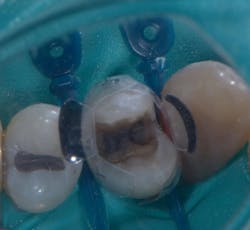

A 68-year-old patient presented with the upper right first premolar with occlusal amalgam and two distal marginal ridge fractures and discoloration under the mesial marginal ridge (figure 1). He previously had an extraction due to a fracture on his lower arch and wanted to treat the upper first premolar proactively. The existing occlusal amalgam was removed under rubber dam isolation. Caries were visualized clinically, and cracks were visualized with transillumination under both marginal ridges (figure 2). The premolar was prepared using a nonretentive cavity preparation design to allow the resin to flow in, out, and around the tooth (figure 3). Particle abrasion with 27 microns at 40 psi (PrepStart, Danville Products) was completed for microretention and biofilm removal before matrices, phosphoric acid etch (figure 4), and adhesive were placed.